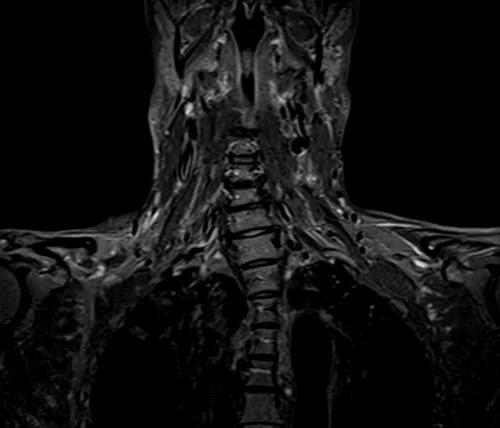

BRACHIAL PLEXUS